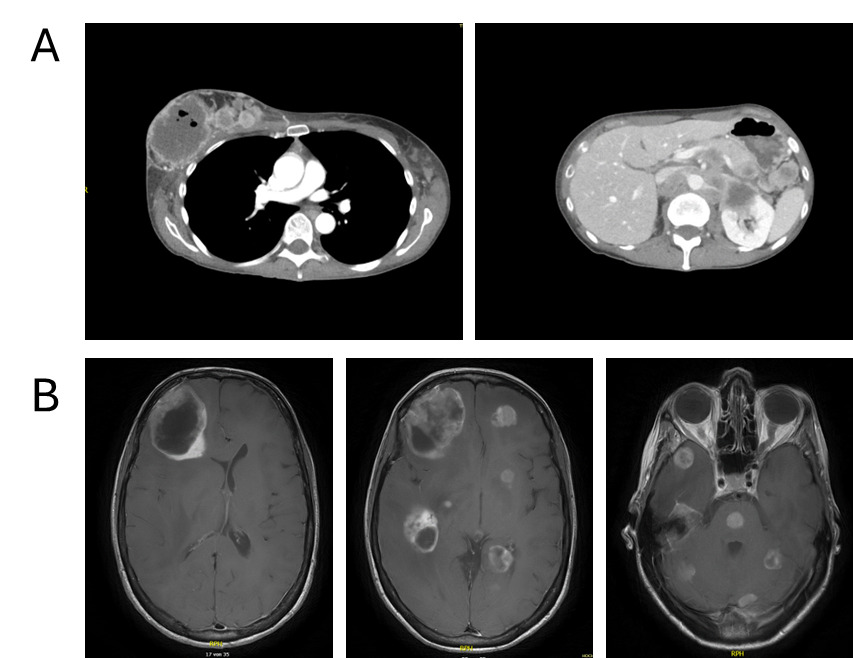

Follow-up in March 2025 showed a marked treatment response after two cycles, with significant regression of intracranial metastases on brain MRI, including resolution of midline shift and cerebral edema, as well as pronounced regression of nodal and visceral disease on contrast-enhanced CT of the thorax and abdomen (Figures 3A and 3B). No new metastatic lesions were identified, consistent with substantial partial remission.

During ongoing treatment, exulceration of the right breast primary tumor developed, indicating an early sign of further disease progression. Initially, it was managed conservatively with oral amoxicillin plus clavulanic acid and referred to specialized wound care. In May 2025, after four cycles of treatment, contrast-enhanced CT and cerebral MRI revealed disease progression involving systemic and intracranial sites (Figures 3C and 3D). Concurrently, thrombosis of the left external iliac vein and new segmental pulmonary emboli in the left lower lobe were detected and therapeutic anticoagulation with apixaban was initiated. Given the radiologic progression on paclitaxel plus pembrolizumab, carboplatin monotherapy was started as an interim measure while reimbursement approval for targeted therapy was pending. However, chemotherapy was discontinued after a single administration at the patient’s request.